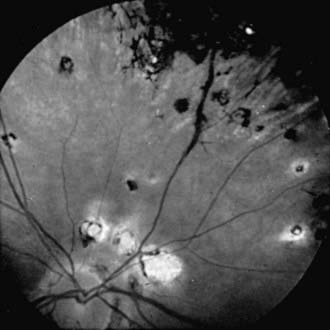

Choroiditis, inflammation of the posterior portion of the uveal tract, invariably also involves the retina; when both are obviously affected, the condition is termed chorioretinitis. The causes of posterior uveitis are numerous; the more common are toxoplasmosis, histoplasmosis, cytomegalic inclusion disease, sarcoidosis, syphilis, tuberculosis, and toxocariasis (Fig. 621-2). Depending on the etiology, the inflammatory signs may be diffuse or focal. Vitreous reaction often occurs as well. With many types, the result is atrophic chorioretinal scarring demarcated by pigmentation, often with visual impairment. Secondary complications include retinal detachment, glaucoma, and phthisis.

Figure 621-2 Focal atrophic and pigmented scars of chorioretinitis.